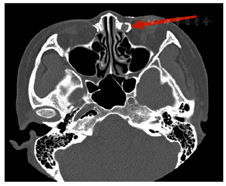

双眼裸眼视力0.8,眼压正常,眼球前后节结构未见明显异常。左眼泪囊区按压可见少许黏稠样黄白色脓性分泌物反流,上下泪小点位正,形圆。泪道冲洗:右眼上下泪小点进针,触及骨壁,冲洗液入咽喉,无反流,不伴脓性分泌物;左眼上下泪小点进针,触及骨壁,冲洗液不入咽喉,上冲下返,下冲上返,伴有黄白色黏稠样脓性分泌物,不伴血性分泌物。庆大霉素尝味实验(−)。双眼前节(−),晶状体透明,眼底未见明显异常。泪道CT造影检查:左眼泪囊窝可见造影剂残留,部分充盈缺损(图1)。

西医诊断:1.左眼慢性泪囊炎。诊断依据,患者青年女性,起病缓,病程长,有流泪、流脓症状,体征:挤压左侧泪囊区可见少许脓液从下泪小点反流;检查,泪道冲洗可见大量黄白色脓液反流,冲洗液未入咽喉;可明确诊断。鉴别诊断,可与"泪道阻塞"鉴别,两者同有流泪症状,但后者不伴流脓,且泪道冲洗不伴脓性分泌物反流,可鉴别。2.左眼泪囊结石。诊断依据,患者左眼泪囊炎,泪道冲洗见脓性分泌物反流,不伴血性分泌物,泪道CT造影显示泪囊窝造影剂残留,部分充盈缺损,泪囊占位明确。

本例为罕见的慢性真菌性泪囊炎合并巨大泪囊结石,起病隐匿,病程长。国内外报道慢性泪囊炎最常见的病原体是细菌,其中46%~90%的病原体是革兰阳性菌,2.5%~40%的病原体是革兰阴性菌,不同地区慢性泪囊炎的微生物谱不同,真菌感染引起的慢性泪囊炎极少见报道[1]。而泪囊结石的病理生理学形成机制至今仍未完全透彻,该病例如此巨大泪囊结石更少见报道。通过本例的诊治过程可以总结学习以下几点:(1)充分了解病史、症状、体征及完善影像学检查对该病诊断及治疗有决定性作用,患者泪道冲洗见脓液反流,不伴血性分泌物等,泪囊CT造影检查见泪囊窝造影剂存留及部分充盈缺损,考虑泪囊肿瘤可能性小、结石的可能性极大。(2)结合病史体征、术前术后检查,该病例考虑为单纯真菌性慢性泪囊炎,该病例真菌性泪囊炎脓液黏稠、呈黄白色,脓液更致密,挤压泪囊区反流较少,术后细菌培养未见细菌生长;而细菌性泪囊炎脓液较稀薄,多为浓液性白色脓性分泌物,临床中可根据脓液黏稠度经验性分析。(3)泪囊结石的形成机制尚不明确,Lynn等[2]研究认为泪囊结石是一种黏肽结石,其位置和病理学成分与泪小管结石不同,所以考虑这两种结石的形成机制也不同。年龄(≤50岁)、性别(女性)、吸烟等被认为是结石形成的诱因。也有学者研究认为泪道结石是由有机物质(包括蛋白质和黏液蛋白,氨基酸含量约20%)组成的"硬"泪石,不含磷酸钙。主要由裂片和小叶组成,中间包含无定形的核,其外包裹体的元素为硅、镁、硫、钾、钙,钠和氯。另外,一些颗粒物中铋、钛、铁和有机纤维的含量较高[3]。Paulsen等[4]发现,泪道结石主要由泪囊上皮细胞和鼻泪管产生的大量的黏液蛋白和三叶草家族(trefoil factorfamily,TFF)中两个肽分子TFF1和TFF3的表达有关,认为可能是这些蛋白质对结石的形成起了作用。而在该病例中泪囊结石的形成与真菌性慢性泪囊炎发生的先后顺序是攻克的难点;巨大泪囊结石形成可导致鼻泪管堵塞,泪囊再感染细菌真菌引发泪囊炎,引起患者流泪流脓等症状;也可能是泪囊真菌感染,引起泪囊、鼻黏膜病理生理学改变,炎症产生阻塞泪道,泪道完全阻塞后炎性坏死物及有机物质结合产生巨大泪囊结石。该泪囊结石后续应做进一步检验及真菌菌属培养等,明确结石内包含的生物化学成分,此为本病例资料收集不足。(4)慢性泪囊炎目前无有效的药物疗法,不同的治疗方法目的均为解除泪道阻塞,重建引流通道。内眦部皮肤径路泪囊鼻腔吻合术(external dacryocystorhinostomy,Ex-DCR)是经典而疗效确切的手术,但存在内眦部皮肤瘢痕、不能同期处理鼻部合并症等缺点。随着临床对泪液引流系统局部解剖和病理生理特点的认识不断深入以及内镜手术系统、微动力系统等设备快速发展和完善,内镜泪囊鼻腔吻合(endoscopicdacryocystorhinostomy,En-DCR)日臻成熟,已成为目前治疗慢性泪囊炎的主要方法之一[5]。本例患者为青年女性,对美观要求高,经沟通后选择微创、美观的鼻内窥镜下泪囊鼻腔吻合术。但于该病例而言难点在于既要完整取出结石,也要鼻腔泪囊吻合成功,术前根据影像检查及鼻内镜下鼻腔检查,选择改良术式下鼻腔泪囊吻合+泪囊取石手术治疗,重点在于术前的泪囊CT造影判断结石大小,术中开窗的大小有利于顺利取石,改良泪囊瓣与钩突黏膜瓣吻合,明胶海绵的使用等是手术成功的关键[6,7,8]。(5)真菌适宜于潮湿、温暖的环境下繁殖,且真菌感染发病增多与感染、机体抵抗力、免疫力降低及菌落失调等因素有关;本例鼻泪管阻塞,泪液积聚泪囊,引流不通畅,为真菌感染营造了良好的繁殖环境,患者在病毒感染感冒的基础上,仍熬夜、饮酒等降低身体抵抗力、免疫力,从而诱发真菌感染;故预防真菌感染,需养成良好的生活习惯,适当锻炼增强身体抵抗力、免疫力,积极防治基础疾病及感染,同时避免滥用药物等。本例在于拓展慢性泪囊炎致病菌的多样性,泪囊结石形成的原因探讨,以及根据临床具体情况及需求进行个性化治疗。